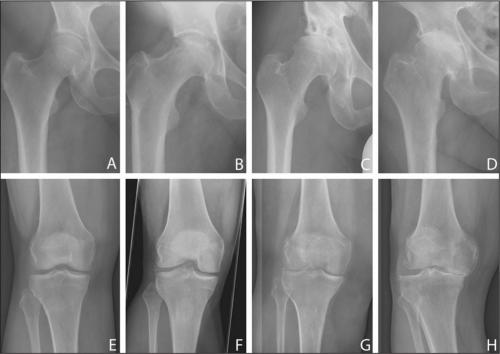

К группе артрозов относится несколько заболеваний, которые по десятой международной классификации считаются синонимами: артроз, остеоартрит, остеоартроз и деформирующий артроз. Особняком стоит коксартроз.

- артрозах (коксартрозах, гонартрозах, артрозах мелких суставов);

Все медикаментозные средства эффективны лишь на I—II стадиях артроза, но бессильны на III и IV. Если в патологию вовлечены не только суставы, но и кости, никакой препарат не поможет. В этом случае избавиться от хронических болей в суставах, трудностей при ходьбе, ограниченной подвижности суставов и других неприятных симптомов можно только с помощью операции.